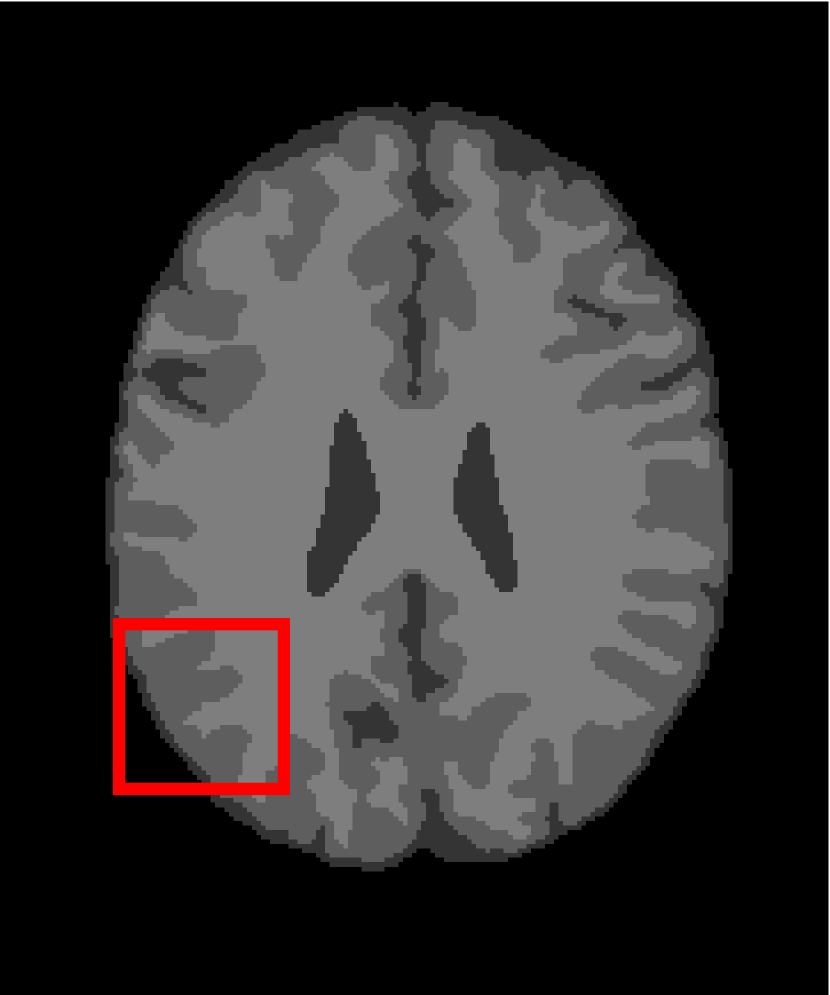

In the second experiments, we segment two medical images coming from a simulated brain database (BrianWeb): http://www.bic.mni.mcgill.ca/brainweb/. The two images are generated by T1 modality with slice thickness of 1mm resolution, 9% noise and 20% intensity non-uniformity. Here, the two images are represented two slices in the axial plane with the sequence of 100 and 110. Moreover, there are golden standard segmentations in the dataset. We set the numbers of clusters to 4. The visual comparisons are illustrated in Figs. 6 and 7.

Figure 7: Segmentation results for the second medical image. From (a) to (l): ground truth, noisy image and results of FCM_S1, FCM_S2, FGFCM, FLICM, KWFLICM, ARKFCM, FRFCM, WFCM, DSFCM_N, and LRFCM.

By focusing on the marked red square in Figs. 6 and 7, we easily find that FCM_S1, FCM_S2, FGFCM and ARKFCM are sensitive to noise. FLICM and KWFLICM are vulnerable to severe intensity inhomogeneity. FRFCM brings overly smooth results due to the use of gray level histograms. WFCM and DSFCM_N cause several contours to change. However, LRFCM acquires clear contours and suppresses noise adequately. Moreover, we find that the segmentation result of LRFCM is closer to ground truth.